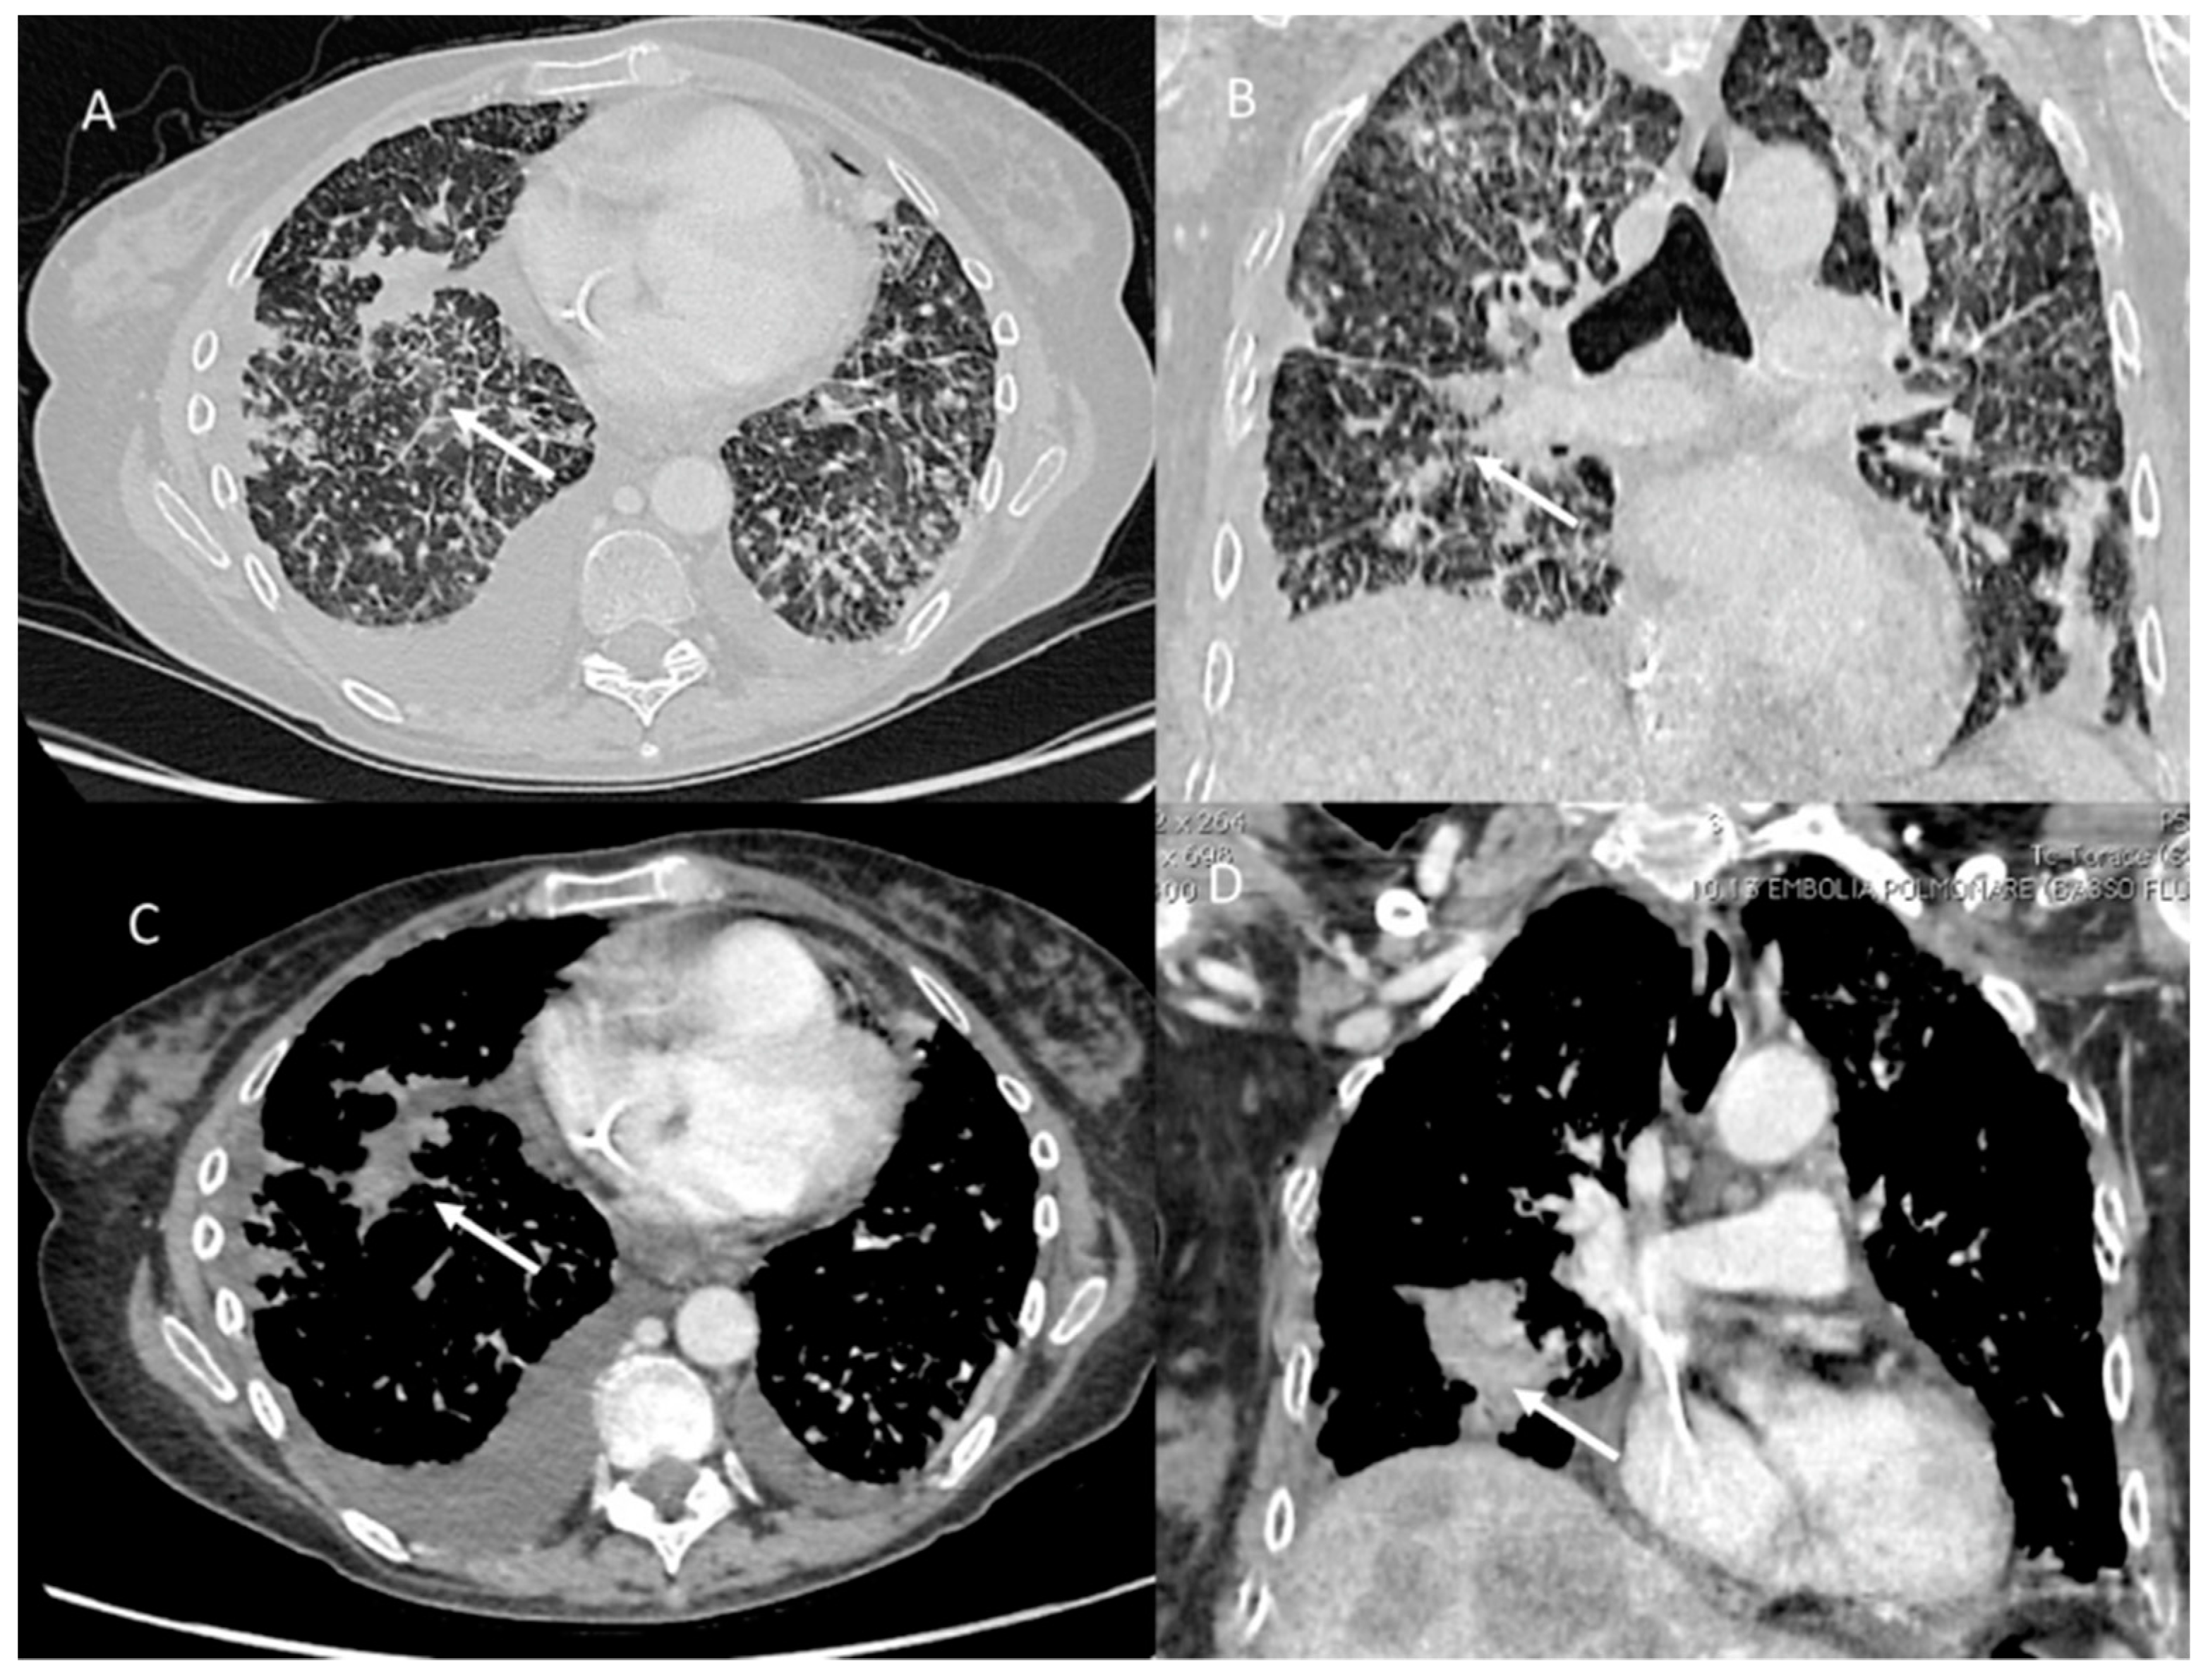

Pulmonary lymphangitis carcinomatosa (PLC) is an unusual appearance of metastatic lung disease in which advanced cancers spread through pulmonary lymphatic vessels (Figure 1).

Figure 1. PLC in pancreatic cancer patient. CT (axial (A,C) and coronal (B,D)) shows comprise diffuse intrapulmonary infiltrates (arrows) with irregularly interlobular septal thickening, nodular thickening and pleural effusions.